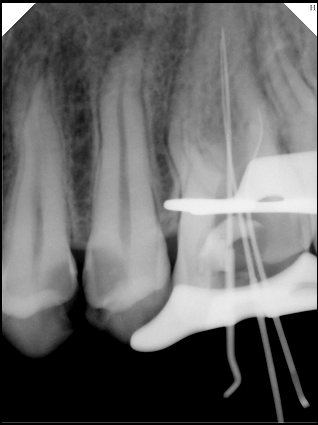

CR/DR 牙齿分割阶段记录

当前进展

- 完成了 CR/DR 牙齿相关分割训练

- 当前结果已经达到阶段预期,但仍有细节问题需要继续处理

相关测试

遇到的问题

- 训练过程中出现过 mask 下移问题

- 部分结果会出现 box 填充异常

- mask 边缘仍然有比较明显的锯齿感

参考